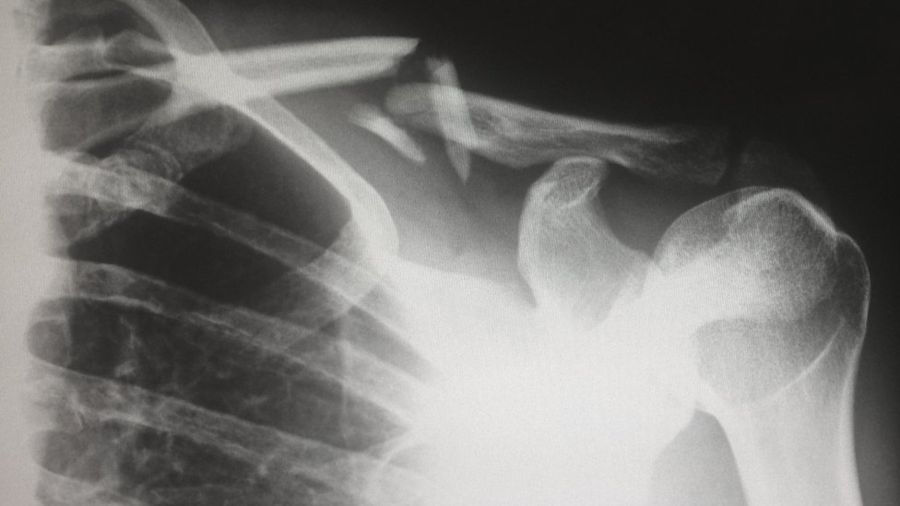

Три главных симптома сломанной кости — боли, отек и деформация.

Если кость развернута на 90 градусов по сравнению со своим обычным положением или вообще торчит сквозь кожу — понятно, это плохой признак.

Еще одно указание на перелом — это щелканье, которое вы услышали в момент инцидента.